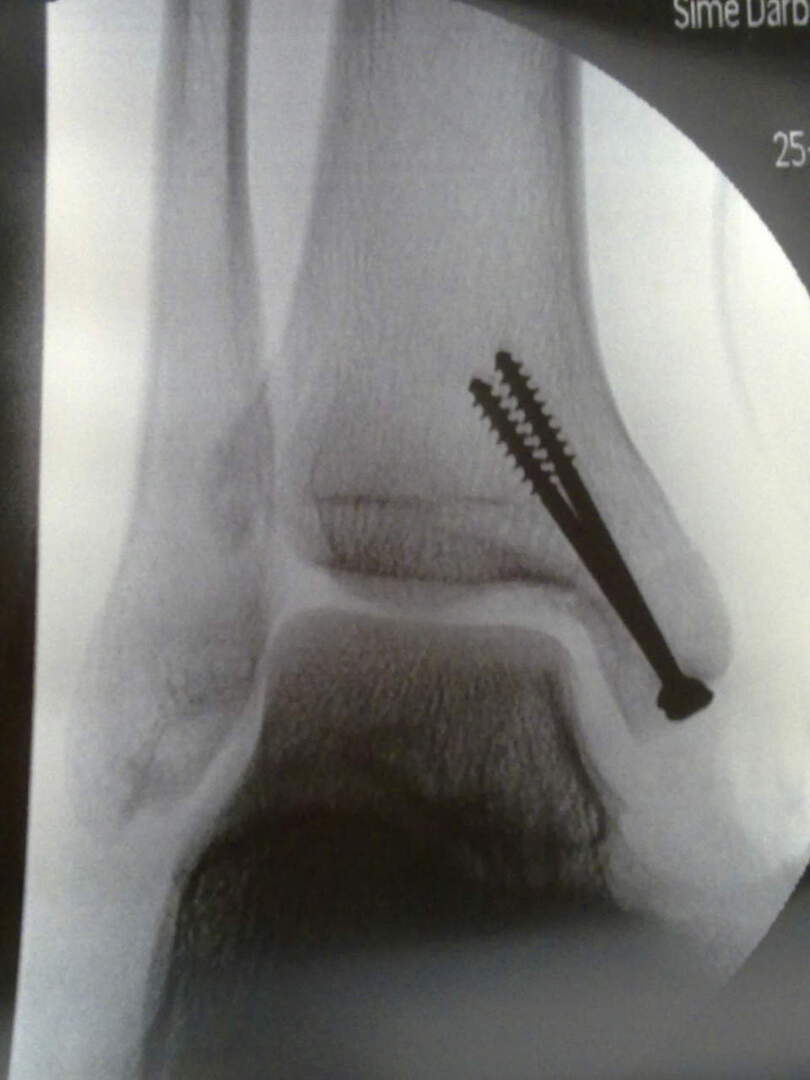

erm...i just got myself 2 stainless steel screw,not serious until whole lower arm gone la taikor (touch wood) :biggrin:

• 09062011656.jpg

09062011656.jpg

44.5 KB · Views: 94